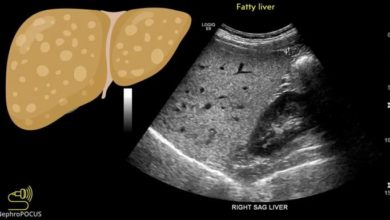

تلك الأعراض قد تشير إلى الإصابة بمرحلة متقدمة من متلازمة الكبد الدهني !

تُعد متلازمة الكبد الدهني أحد المشكلات الصحية التي تنتج عن تراكم الدهون في الكبد، ويُعتبر الأشخاص الذين يعانون من زيادة…